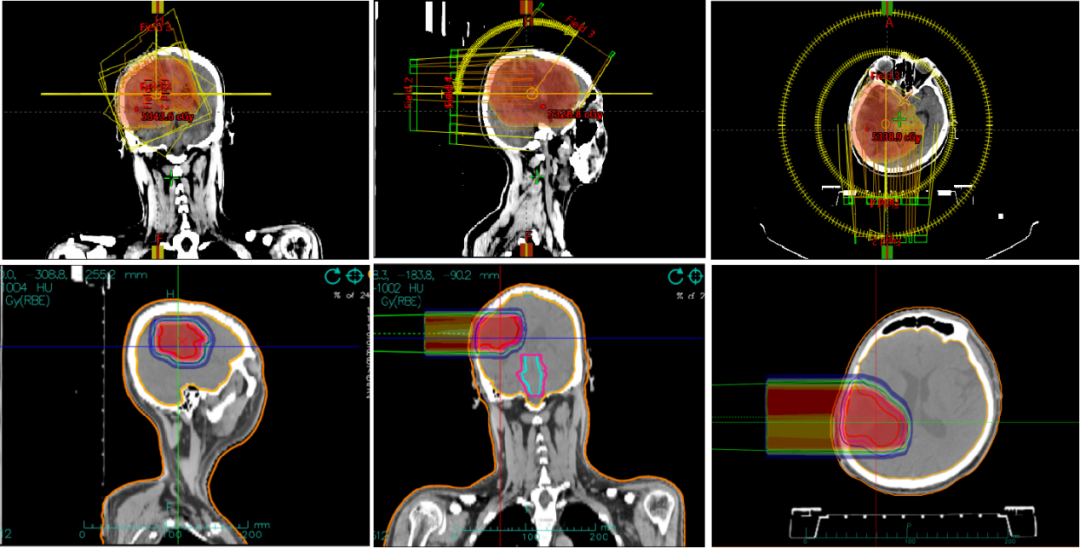

33岁,回族,入院3月前行脑胶质瘤手术,病灶大部分切除,但仍有残留,术后肢体无力未缓解,诊断为:(右侧额顶叶)胶质母细胞瘤 WHO IV级,治疗前左侧肢体肌力3级,治疗后左侧肢体肌力基本恢复。

图5 光子联合碳离子治疗剂量图

图6